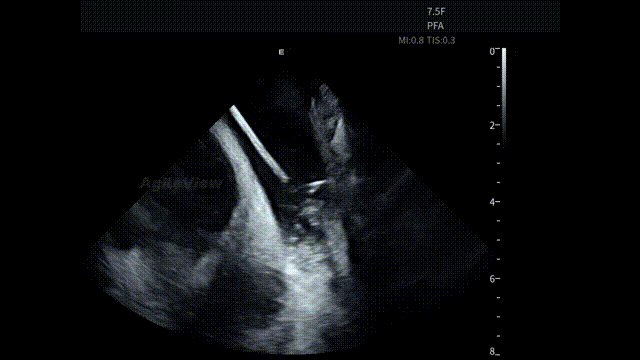

术中,基于AgileView™ ICE 7.5F的产品优势,蒋晨阳主任团队将ICE导管打A弯跨三尖瓣进右室,松弯卡室上嵴,顺转后打到左房长轴切面,以便更好地进行导管封堵/贴靠与位置的判断,在AgileView™ ICE实时影像的指导下,PulseSelect™ 脉冲消融导管安全进入左心房,先后完成双侧肺静脉隔离及MTI、roofline、后壁BOX、SVC隔离, ICE下可见导管贴靠良好,整个消融过程顺利,消融时间约50分钟。术后患者恢复良好。

房间隔穿刺-导丝进入上腔

房间隔穿刺

导丝进LSPV

左房长轴一嵴部贴靠

RSPV

SVC